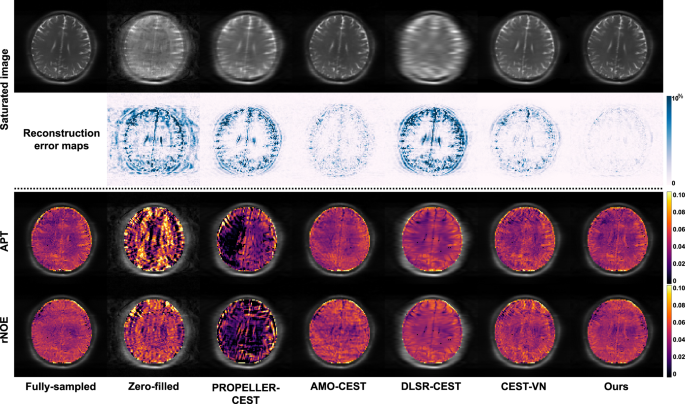

The quantitative evaluation results for all compared methods are summarized in Table 1, which lists the average and standard deviation of PSNR and SSIM for both 3\(\times\) and 6\(\times\) undersampling. Our method outperforms all compared methods for both Cartesian and spiral k-space trajectories. In addition, we performed Wilcoxon signed-rank tests on both PSNR and SSIM results, yielding \(p\)-values of \(p\ll 0.0001\) for all compared methods, i.e., statistical significance. Figure 2 shows qualitative evaluation results of all compared methods. The reconstructed images and their corresponding error maps (relative to fully sampled images) are shown. The error maps are computed using the formula \(100 \% \times \left|\hat{x}-x\right|/{\max }_{95 \% }\left(x\right)\), where \(\hat{x}\) represents the reconstructed images, and \(x\) denotes the fully sampled images. All error maps are displayed using the same color scale. Our method achieves higher consistency to fully sampled images, with enhanced image fidelity and fewer structural distortions visible in error maps.

Quantitative evaluation results are summarized in Table 2, including mean and standard deviation values for both PSNR and SSIM metrics. Our method significantly outperforms all compared methods by a large margin (\(p\) ≪ 0.0001, Wilcoxon signed-rank test). Figure 7 displayed representative saturated images and corresponding CEST maps at 6\(\times\) undersampling. According to error maps, our method yields more consistent results for fully sampled images. Figure 8 presented reconstructed images from the 5th and 15th receiver coils at 6\(\times\) undersampling. Individual coil images exhibited relatively low SNR and strong signal intensity decay with increasing distance to the receiver coil. Our method demonstrates better image fidelity. In this work, a two-step training strategy was proposed to effectively leverage multi-coil information. During pretraining, our method was trained on individual coil data, achieving SSIM/PSNR values of \(0.9815\pm 0.0547\)/\(40.7928\pm 1.8572\) (\(3\times\) undersampling) and \(0.9634\pm 0.0914\)/\(37.8063\pm 1.0193\) (\(6\times\) undersampling). In the finetuning stage, we incorporated a differentiable coil combination layer to further optimize the output coil-combined images. This multi-coil refinement stage provides additional performance gains beyond the individual coil results, achieving SSIM/PSNR values of \(0.9825\pm 0.0128\)/\(43.8960\pm 1.8080\) (\(3\times\) undersampling) and \(0.9652\pm 0.0365\)/\(41.0399\pm 1.0433\) (\(6\times\) undersampling).

Human brain imaging with different acceleration rates

Five CEST scans were acquired on the clinical MRI scanner, and reconstruction performance was evaluated via five-fold cross-validation. Similar to the rodent brain study, here we performed \(3\times\) and \(6\times\) undersampling, which was applied to the k-space of each individual coil. For \(3\times\) and \(6\times\) complementary undersampling, 16 and 8 central k-space lines were densely sampled, respectively, while the peripheral k-space was covered by \({N}_{{{\rm{adj}}}}=5\) and \({N}_{{{\rm{adj}}}}=11\) adjacent frequency offsets in a cyclic manner. All other parameters, including the comparative deep learning methods, remained consistent with those used in the rodent brain study. Because of the long computation time and low reconstruction performance, CS-Wavelet was excluded from the human brain study. For each comparative method except CEST-VN, reconstruction was performed on individual coil data rather than on coil-combined images. Coil-sensitivity maps were estimated from reconstructed k-space using ESPIRiT68. Final coil-combined images were generated using the SENSE algorithm69. CEST-VN here followed the original multi-coil implementation.